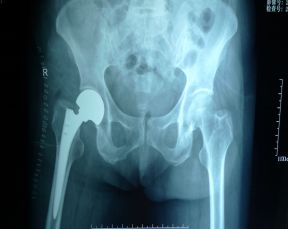

患者李某,女性,69岁,因外伤后右髋部疼痛,活动受限2小时,在市内多家医院就诊,均因难度较大而未能手术。患者转诊到我院骨四科后,经缜密检查后,确诊为右侧股骨颈骨折。经科室会诊讨论,充分评估病情,完善各项术前准备,决定为患者进行前侧入路切口,开展髋关节前路人工关节置换术,由燕飞主任主刀。术中,为保护股外侧皮神经,患者取侧卧位,患髋伸直位,随后,医生沿髂前上嵴与髌骨外缘连线近端做了长约6~10cm的直切口,切开皮肤、皮下组织,沿阔筋膜张肌和缝匠肌间隙钝性分离至血管间隙,结扎血管,向内牵开股直肌,显露关节,对股骨颈进行双道截骨,在适当下肢牵引下取出截骨块,用取头器取出股骨头,将膝关节屈曲90°、髋关节外旋90°,充分暴露股骨髓腔,用一把带弧度的刮匙打开股骨髓腔,用双偏置式髓腔锉从最小号开始逐级扩髓,直至合适大小,安装股骨头颈领及试模,试模位置透视合适后置入股骨柄假体及股骨头假体,关节复位后放置引流管。

据悉,人工髋关节置换术历经一个多世纪的发展,已经成为治疗髋部关节疾病的标准手术之一。近年来,随着手术入路改良、手术工具优化、假体材料更新,DAA全髋关节置换术越来越显示出优越性。它所具有的优势如手术创伤小、术后并发症少、康复快、低假体脱位风险等。该技术具有缓解疼痛,改善关节功能,恢复关节的稳定和肢体的功能等优点,已得到广大患者的认同并迅速推广。然而,DAA全髋关节置换术对我市医疗人员来说,仍然是难度较大的高精尖手术,患者以往都到省级医院才能得到治疗。我院此项技术的成功开展填补了通辽市空白,为深受骨科疾病困扰的广大患者带来了福音。